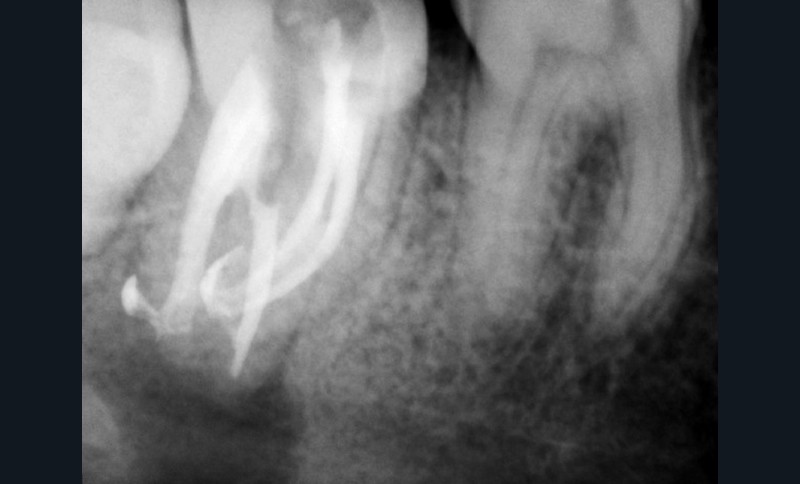

Si l’étude de Peters [18] nous montre que l’instrumentation laisse 35 % du volume canalaire non instrumenté, Ricucci et Siqueira montrent que la préparation physico-chimique n’élimine que partiellement les tissus nécrotiques à l’entrée des canaux latéraux, des isthmes et des ramifications apicales, en laissant des tissus enflammés et infectés, en association avec des lésions apicales [29] (fig. 4 et 5).

Fig. 4 – Coupe d’une racine mésiale de molaire mandibulaire avec deux canaux traités. Coupe à 3 mm de l’apex, coloration Brown et Brenn, technique modifiée par Taylor. Ces images montrent un isthme étroit avec une infection bactérienne, ce qui prouve l’importance de désinfecter et d’inclure l’isthme dans les traitements conventionnels et dans les rétropréparations apicales en chirurgie endodontique.